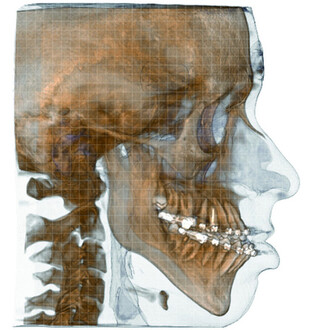

- Moderne 3D-Planungsverfahren (VSP-virtual surgical planning) und CAD/CAM Technologie

- Moderne 3D-Planungsverfahren (VSP-virtual surgical planning) und CAD/CAM-Technologie

Ein individuelles Behandlungskonzept wird in enger Absprache mit dem behandelnden Kieferorthopäden und mittels modernster digitaler 3D-Planung erstellt.